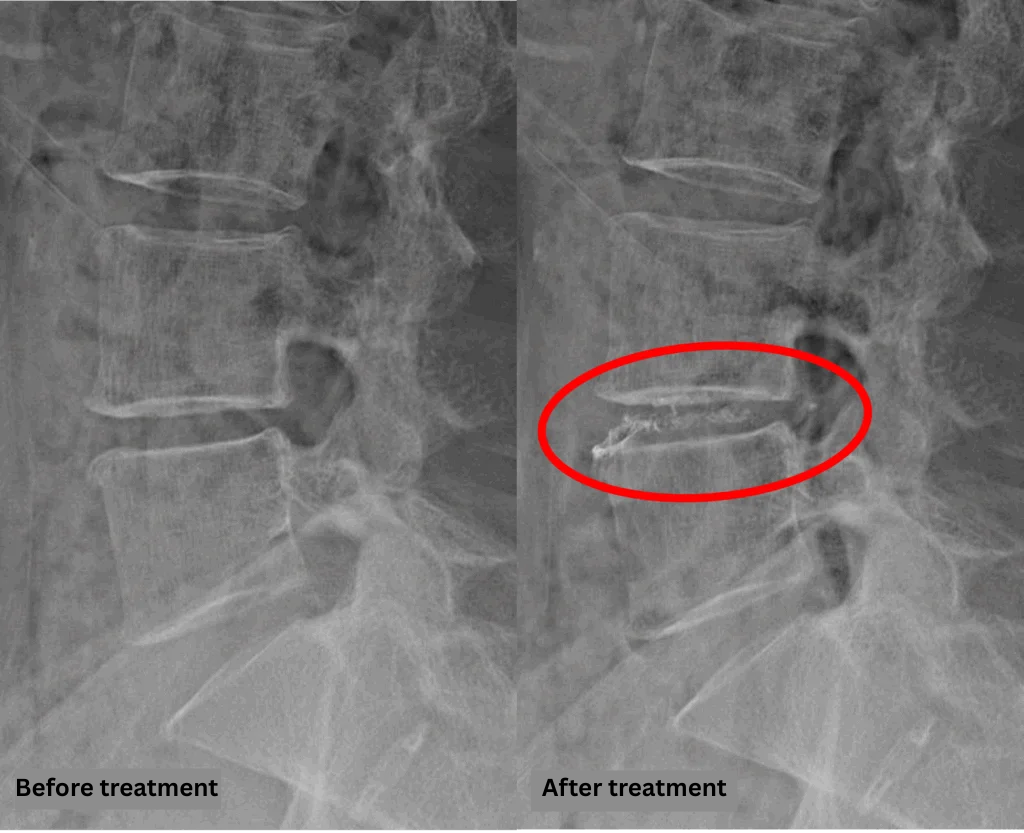

- L4/5: Disc degeneration, bulging, and foraminal stenosis were observed.

The above findings were also observed on the imaging.

Compression of the spinal canal due to the L4/5 disc pathology was considered the most likely cause of the patient’s symptoms.

After consulting with the patient, the Cellgel Method was performed on L4/5.